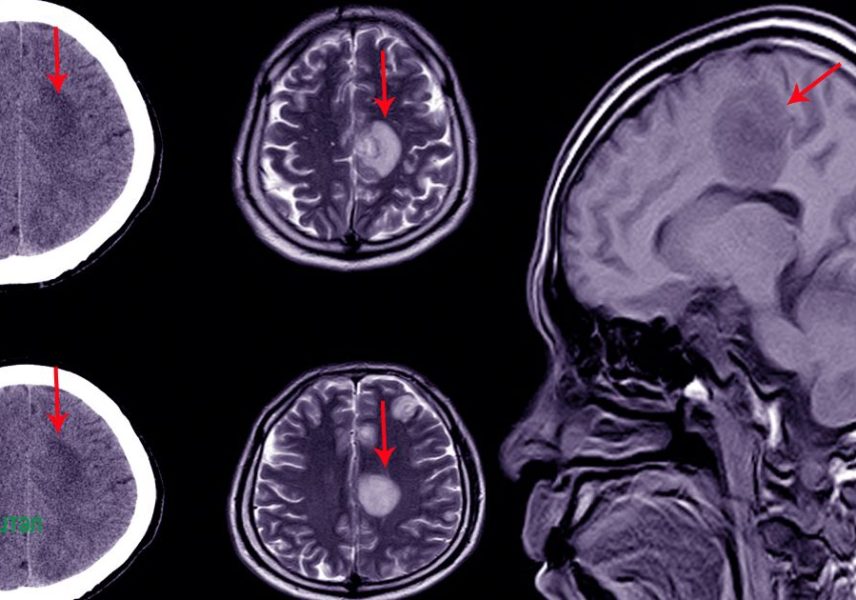

Преди всичко проблемът хидроцефалия е изразен в упражняване на повишено налягане около мозъчни дялове. Моментът неминуемо се свързва с хронично необяснимо главоболие. На помощ, независимо от пациентската възраст, идва образната диагностика, ядрено-магнитният резонанс.